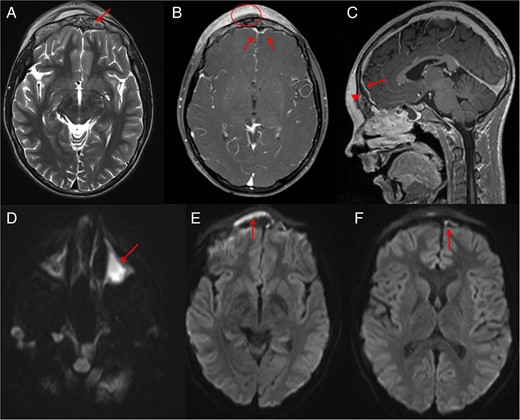

Two days following this procedure, the patient had persistent tenderness over the forehead. At this point, we decided to proceed to magnetic resonance imaging (MRI) (Fig. 2) to further evaluate the frontal bone and extra-axial spaces. These images confirmed abnormal signal within the frontal bone in keeping with osteomyelitis. Post-contrast-enhanced images demonstrated scalp and intra-dural enhancement. Diffusion-weighted images confirmed an evolving epidural abscess that was encroaching and slightly compressing the superior sagittal sinus, although the sinus remained patent with no evidence of thrombosis.

Post-drainage of right maxillary sinus and right orbital subperiosteal abscess MRI was performed. MRI shows abnormal signals (arrow) from the anterior frontal bone suggesting osteomyelitis (A). Post-contrast MRI demonstrates the scalp Pott's puffy tumour (circle) with surrounding scalp enhancement. MRI (B) also shows reactive dural enhancement and an epidural abscess that is better seen (arrowhead) on sagittal sequence (C) compressing the superior sagittal sinus (arrow) which is not thrombosed. Diffusion images (D–F) confirm pus in left maxillary sinus (D), scalp subperiosteal abscess (E) and intracranial extra-axial (F) epidural abscess (arrows).

In paediatric patients, clinical symptoms can often be non-specific and vary depending on the severity of infection; a rather indolent course may consist of headache, rhinorrhoea and fever. There should be a high index of suspicion for Pott's puffy tumour when patients develop a fluctuant, tender swelling of the scalp. CT is an excellent initial imaging modality as it is fast, readily accessible and shows good bony detail. If there are any neurological signs such as those of raised intracranial pressure, nausea, vomiting or a focal neurological deficit, there should be a low threshold for MRI and should include post-contrast and diffusion-weighted images. In our case, even with the absence of initial neurological signs, MRI was still performed as it helps to determine the full extent of intracranial involvement that may not be initially evident [4] (Fig. 2).